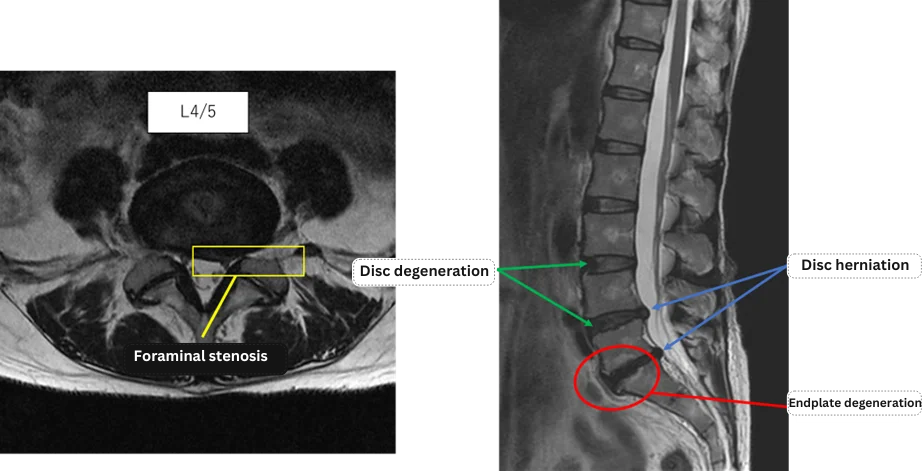

Imaging and findings

L1/2: No abnormalities

L2/3: No abnormalities

L3/4: No abnormalities

L4/5: Disc degeneration, lumbar disc herniation, left foraminal stenosis

L5/S: Disc degeneration, lumbar disc herniation, endplate degeneration

The above findings were also observed on the imaging.

These findings indicate that abnormalities at L4/5 and L5/S (disc degeneration, herniation, left foraminal stenosis, and endplate changes) are highly likely to be the primary cause of symptoms.